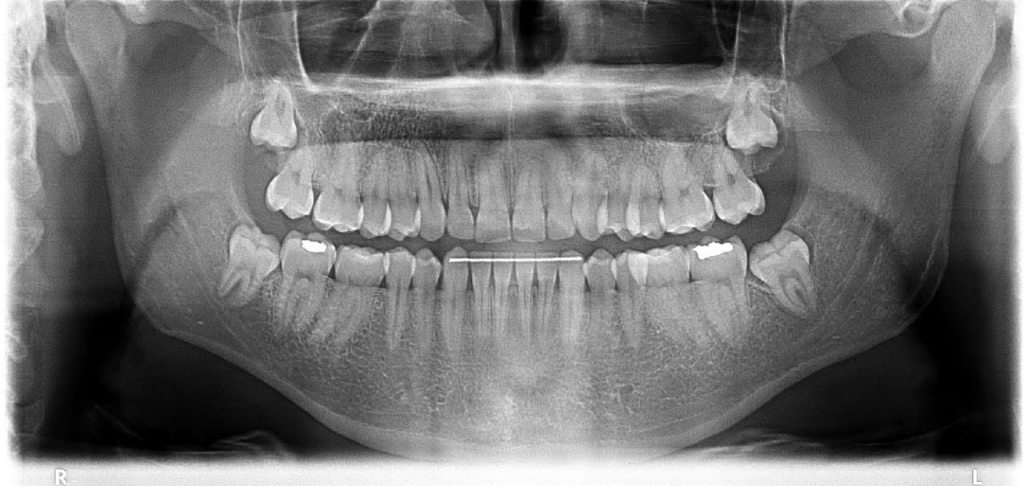

Diş röntgeni diş, çene kemikleri ve diş eti seviyesinin klinik muayenede görülmeyen kısımları hakkında fikir edinmek amacıyla X ışını yardımıyla elde edilen radyolojik görüntülerin adıdır. Diş röntgenleri tedaviye başlanmadan önce teşhis, tanı ve planlama amaçlı istenebileceği gibi, tedavi süresince ve tedavi sonrasında kontrol amaçlı olarak da istenebilmektedir.